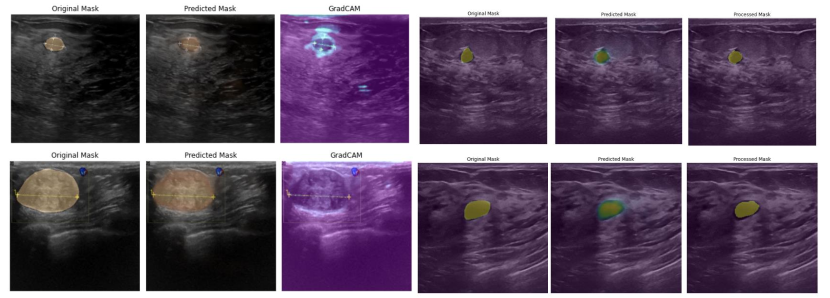

4.2 Evaluating trained Proposed architecture

AttentionUNet/UNet is the best know model for Multi-Class Segmentation, thats why we will be creating an Attention UNet Model. As the image Dataset is old, please do not use it for any new medical operations.

All the images are 500 X 500 pixels. RAM will not be enough so we will resize the Image to 256 X 256 pixels. In this experiment, the histogram equalisation is followed by training of the ViT model for breast picture segmentation. The U-Net architecuture will consist of an Encoder Block, Decoder Block and an Attention Gate. Our system is evaluated using the standard standards for segmentation model evaluation. Fig. depicts the accuracy and loss learning curves for model training and model validation. These learning plots show a well-fitted learning algorithm because both the validation and training curves maintain a stable point with little gap. Performance was increased by incorporating three tasks into the training of the effective UNet model [16] at once: computing output, troubleshooting errors, and fine-tuning hyper-parameters. The maximum training and validation accuracies are 95% and 99%, respectively, after numerous iterations of tuning the hyper-parameters, which are accomplished with an idea. For Further analysis of the proposed architecture the appropriate experimental parameters have been taken into consideration, such as IoU, Loss, Accuracy, Precision, Recall, F1-Score, etc.

4.2.1 Observations

-

•

After 12 epochs model, the segmentation model results are outstanding.

The model was quickly able to detect black round spots but failed when the shape was irregular (Not the case with the current model because it is trained with high Steps Per Epoch (SPE)).

It also gets confused between the dark areas, which makes sense.